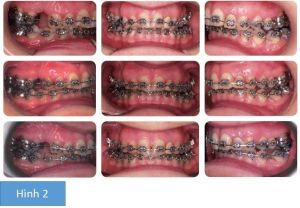

Phân tích case: Niềng răng, phẫu thuật hàm và phẫu thuật làm nhỏ cằm cho khách hàng nữ 42 tuổi

Bệnh nhân nữ 42 tuổi có khớp cắn hạng II trên nền xương hạng II trung bình với tỷ lệ theo chiều đứng trung bình. Đỉnh cằm hơi lệch trái. Mút môi, môi dưới nằm dưới các răng cửa trên ở tư thế nghỉ. Góc mũi môi bình thường nhưng hàm dưới lùi và đỉnh cằm nhô dẫn đến kết quả là môi ở tư thế nghỉ nằm lùi phía sau đáng kể so với đường E và do đó, kiểu mặt nghiêng xấu.

Điều gì đã xảy ra với R22?

Mắc cài được gắn lên mão sứ, bị bog ra và thất lạc trước phẫu thuật! Thay vì gắn nó lại, bác sĩ quyết định để mặc nó tới sau khi phẫu thuật xong và thay thế nó trước khi tinh chỉnh khớp cắn cuối cùng.